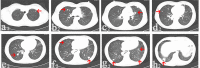

Materials and methods: We retrospectively reviewed seven patients with pulmonary metastatic GCT who received denosumab treatment after local tumor surgery during January 2014 and July 2016. Denosumab treatment for all patients lasted for at least 12 months. Serial chest computerized tomography scan was used to monitor the drug response and RECIST 1.1 standard was used to evaluate the therapeutic efficacy.

Results: All patients experienced chest pain relief in the first month of treatment. Three patients showed partial response. Four patients got stable disease after denosumab treatment. Adverse events included one patient with hypocalcemia and two patients with fever. No treatment-related deaths were reported. No patient with metastatic disease progression was found during an average of 28.6 months follow-up period.